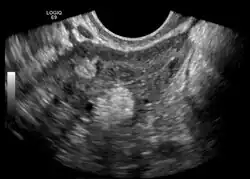

Die Dermoidzyste (früher auch Dermoidgeschwulst[1], im Volksmund auch fälschlich Zwilling[2] oder Zwillingsgewächs[3]) ist ein Hohlraum, der von Oberhautgewebe ausgekleidet ist. Die Dermoidzyste gehört zu den Teratomen.

Eine Dermoidzyste ist ein Keimzelltumor, ein reifes Teratom, das aus vollkommen verschiedenen Gewebearten besteht. Daher kann es innerhalb der Zyste zur Ausbildung von Gewebestrukturen wie Muskulatur, Knorpel, kleinen Knochen, Haaren und auch völlig ausgebildeten Zähnen kommen.

Eierstock

Im Gegensatz zu den Zysten, die während des weiblichen Regelzyklus entstehen und sich zumeist von selbst zurückbilden, ist die Dermoidzyste eine embryonale Fehlentwicklung.

Bei großen Dermoidzysten steigt das Risiko einer Stieldrehung (Torsion). Bei einer derartigen Komplikation sowie bei einer Einblutung wird eine operative Entfernung, meist durch Laparoskopie, erforderlich.[4][5]